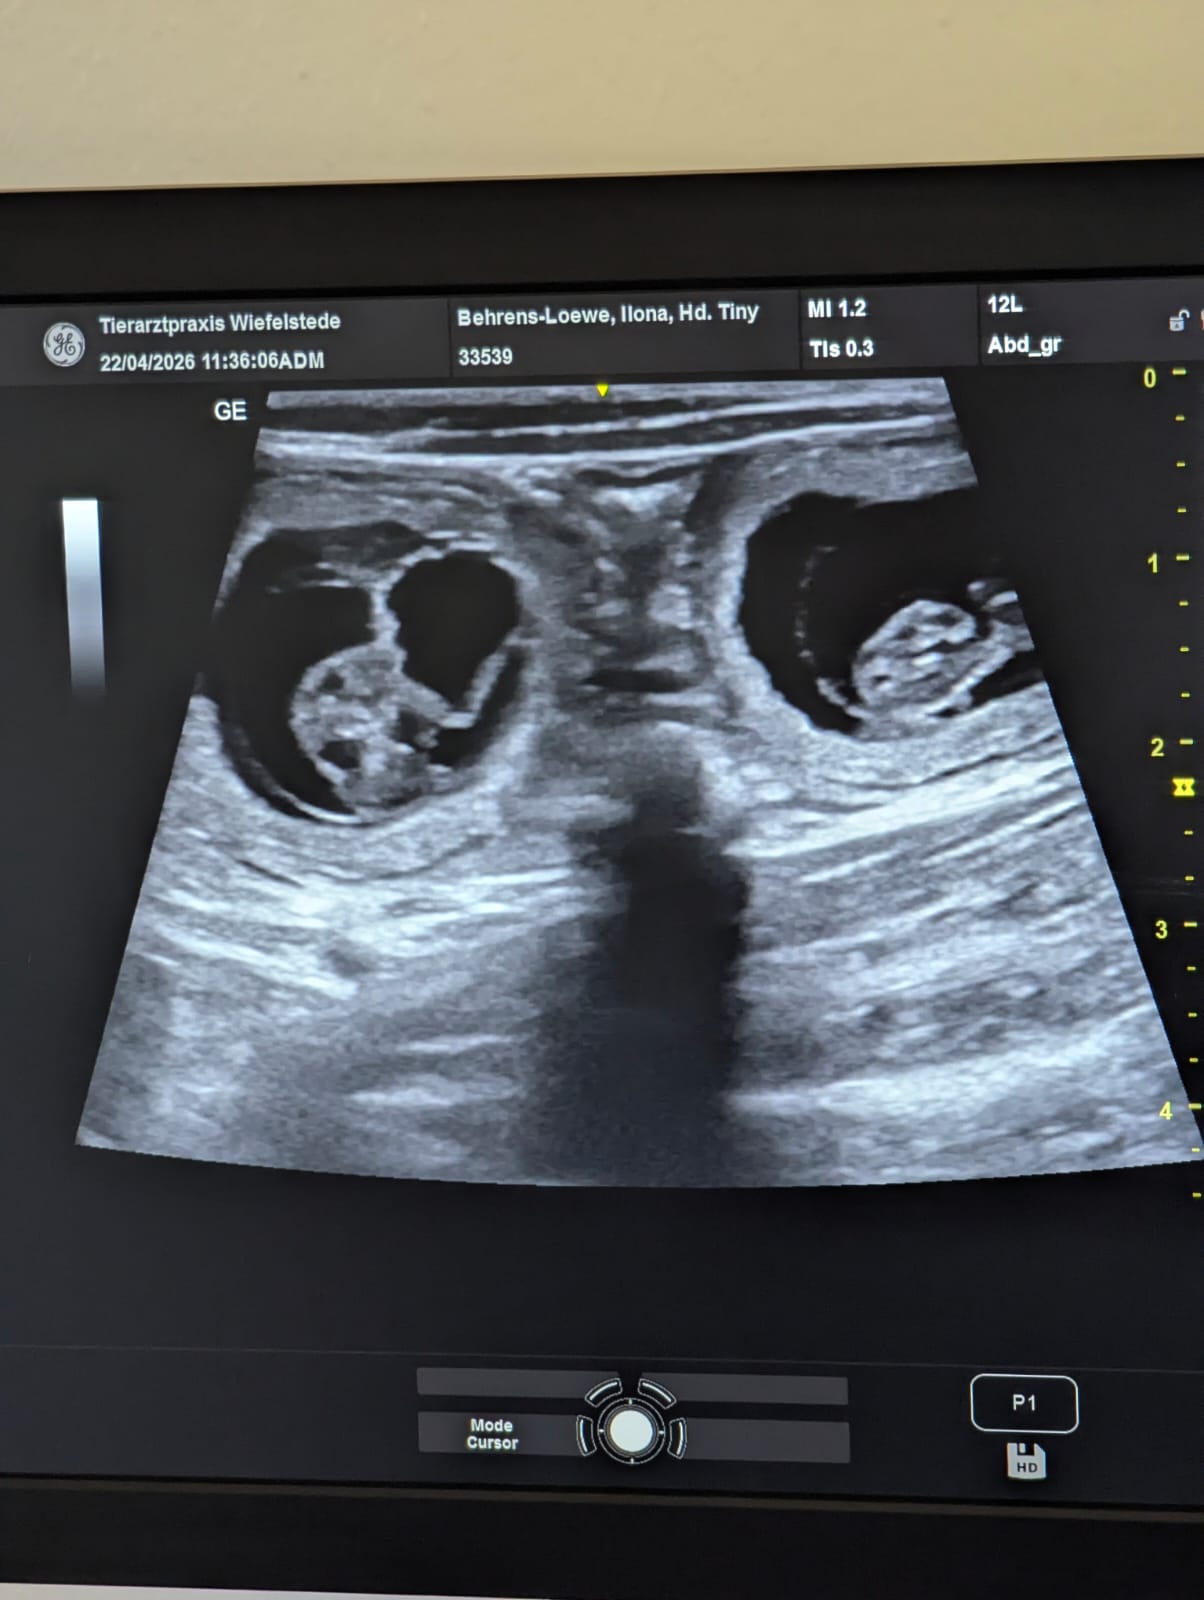

🥰 Wunderschöne Nachrichten 🥰

Geburtstermin Ende März

Neuigkeiten von Culann's Amor

Stammbaum Vorschau vom Culann's E Wurf

Freudige Nachrichten !!!

Culann's Amor und Culann's Bahira haben eine schöne Zeit miteinander verbracht ....

Weitere Informationen zu gegebener Zeit - also bleibt gespannt !